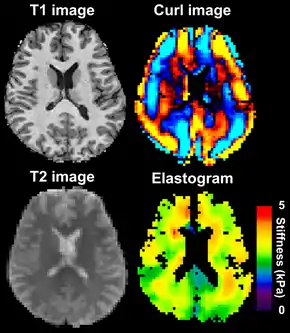

Magnetic resonance elastography (MRE) is a non-invasive medical imaging technique that measures the stiffness of soft tissues by generating shear waves in tissue, imaging their propagation using MRI, and processing the images to generate a stiffness map (elastogram).[1] It is one of the most commonly used elastography techniques.[2]

![]() Magnetic resonance elastography of the brain. A T1 weighted anatomical image is shown in the top-left, and the corresponding T2 weighted image from the MRE data is shown in the bottom-left. The wave image used to make the elastogram is shown in the top-right, and the resulting elastogram is in the bottom-right. | |